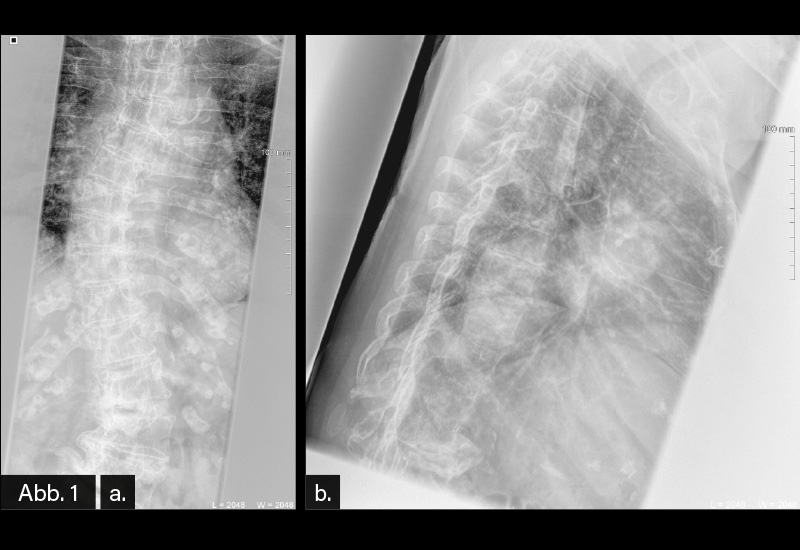

BILDGEBENDE DIAGNOSTIK: Röntgen (s. Abb. 1/ Abb. 2)

DIAGNOSE: Fortgeschrittene langjährige Torsionsskoliose mit Abstützungsreaktionen

Die Diagnose wird mit der konventionellen Röntgendiagnostik gestellt. Zur genauen Beurteilung ist eine Aufnahme der BWS und LWS (auch in Form einer Ganzwirbelsäulen-Röntgenaufnahme) im aufrechten Stand notwendig. Idealerweise werden zusätzlich die Beckenkämme zur Bestimmung des knöchernen Wachstumsstatus sowie die Schlüsselbeine zur Bestimmung des Schulterstandes abgebildet. Die Diagnose wird jedoch erst gestellt, wenn zusätzlich eine Rotationsabweichung besteht. Die seitliche Röntgenaufnahme vermittelt Informationen über das sagittale Profil. Die Abbildung des Beckens und der Hüftgelenke auf der seitlichen Röntgenaufnahme ermöglicht die Bestimmung der Wirbelsäulen-Becken-Relation. Das Becken besitzt bei sagittalen Wirbelsäulendeformitäten die Möglichkeit der kompensatorischen Rotation um die Oberschenkelköpfe, wodurch es zu einem Wiederaufrichten der Wirbelsäule kommt.